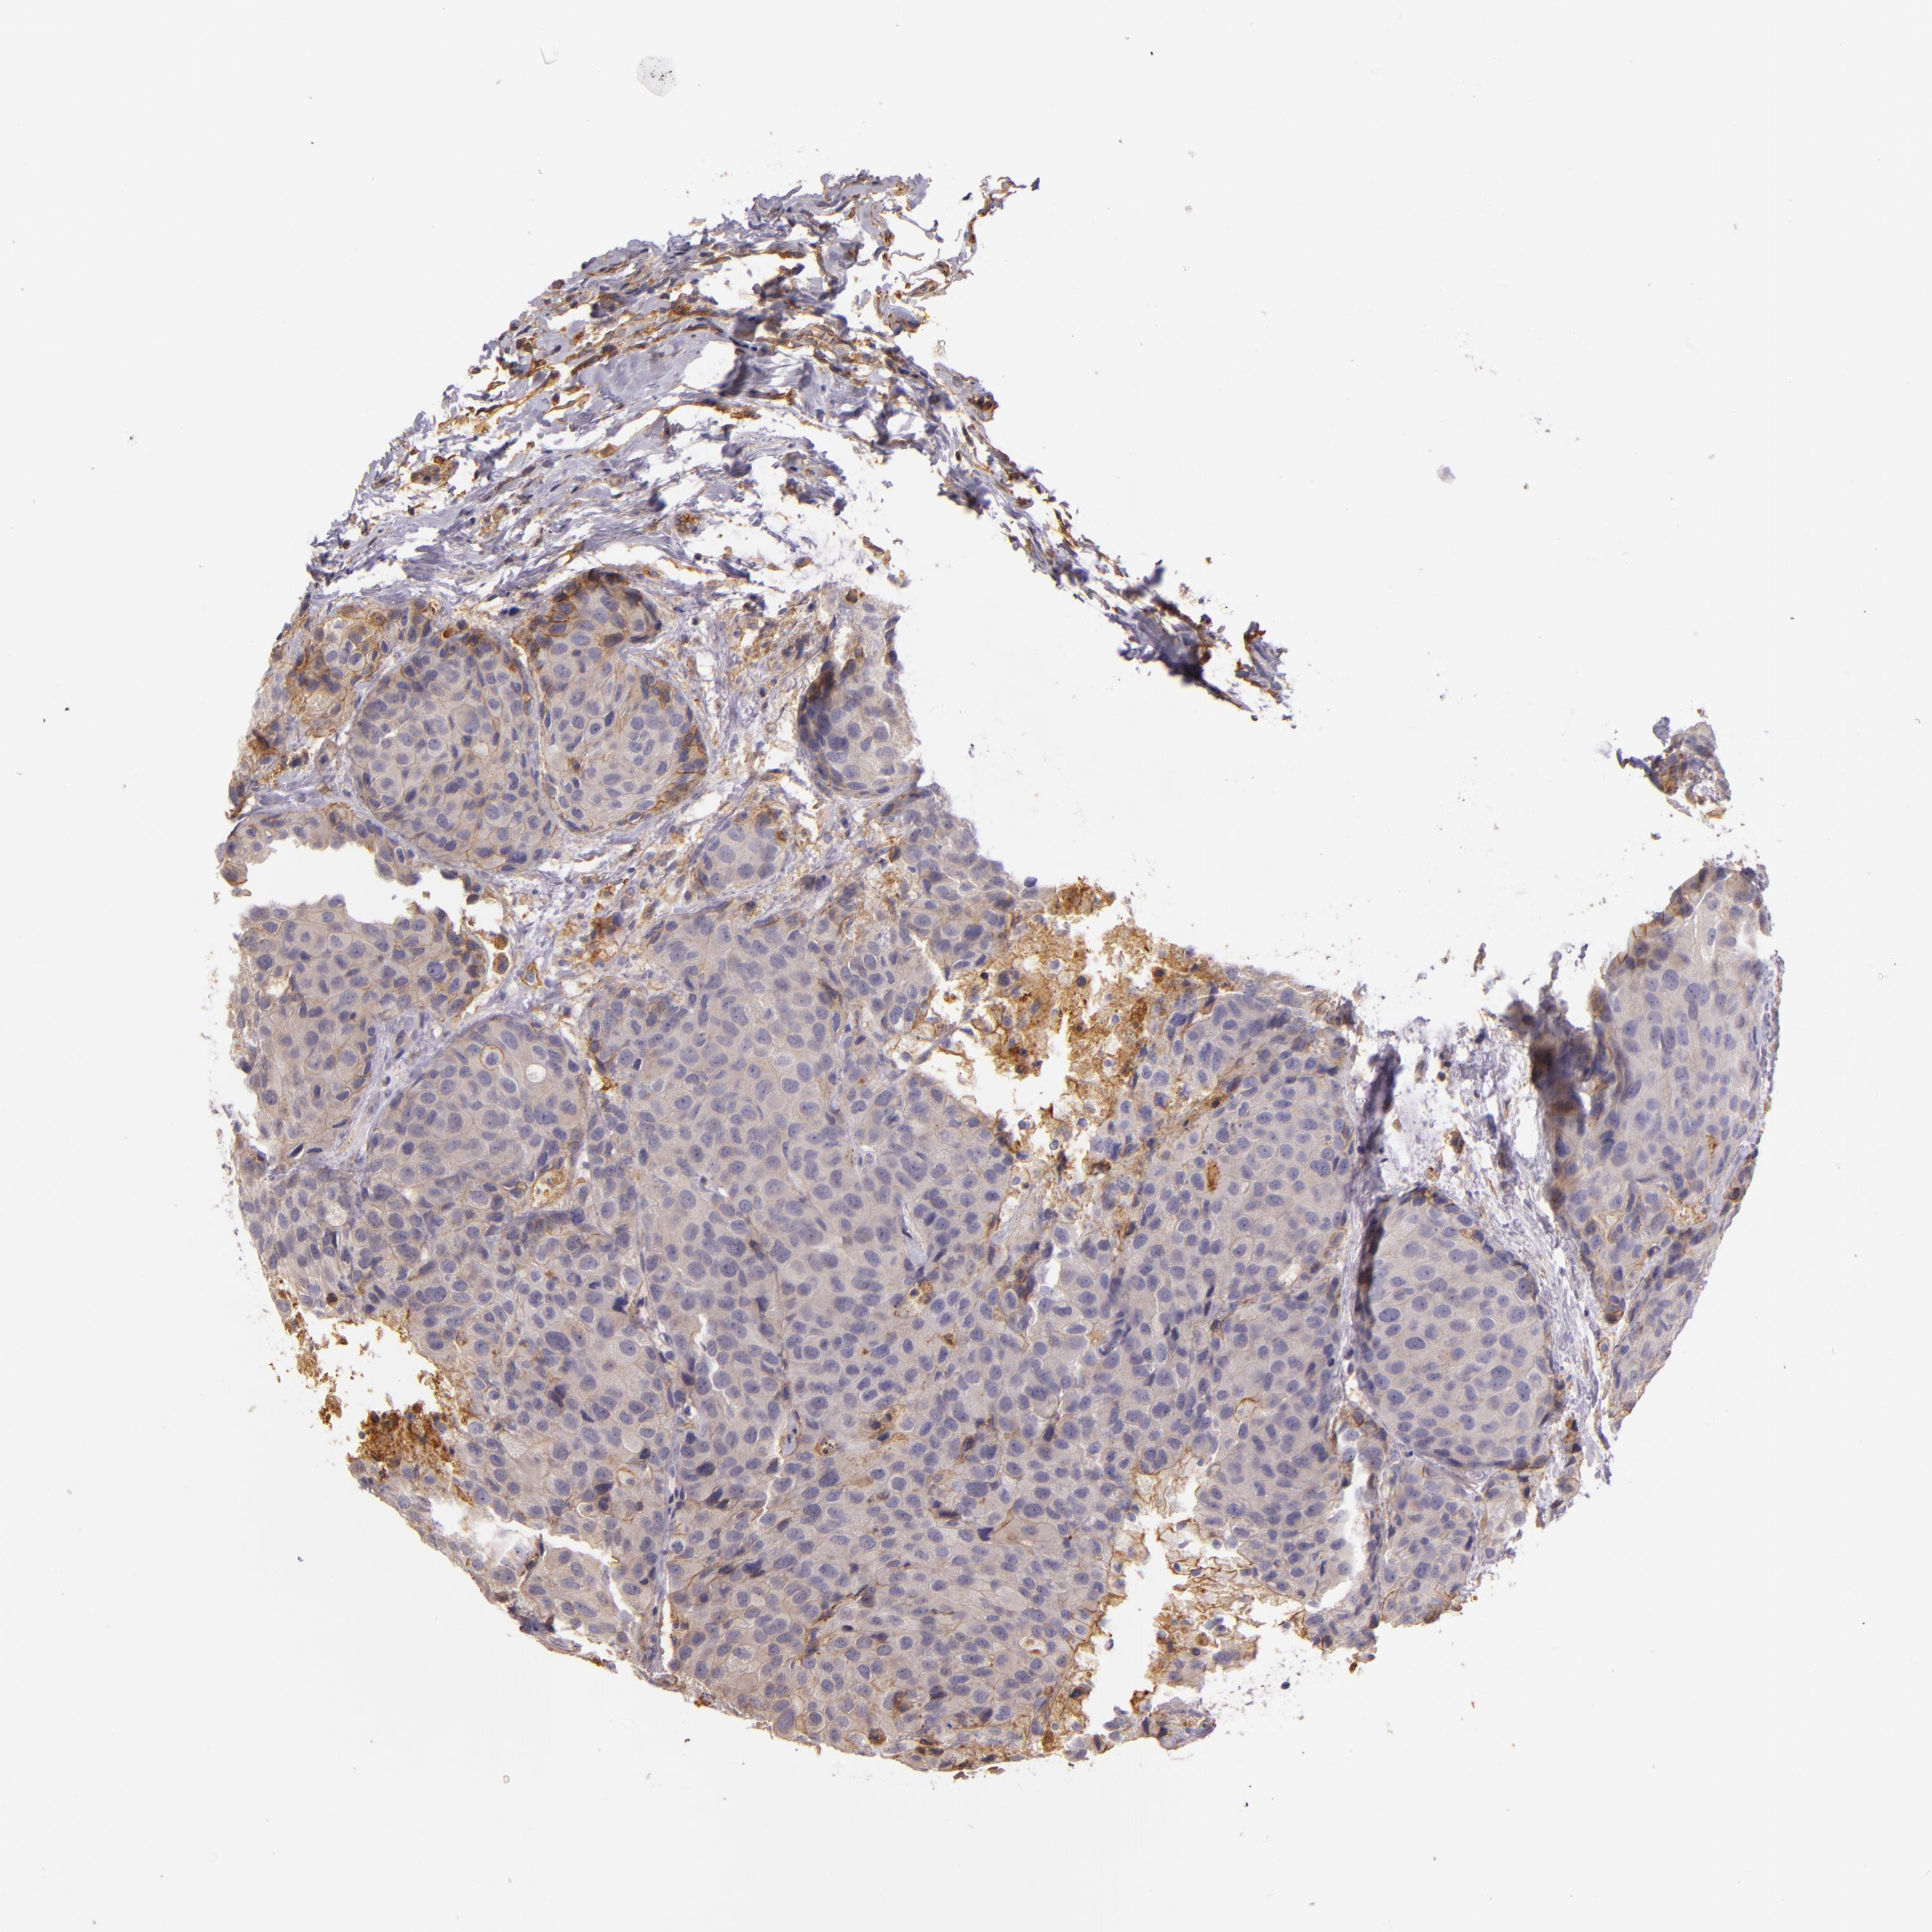

BRCA TCGA BRCA VALIDATION PROTEIN EXPRESSION

Breast cancer

Human cancer